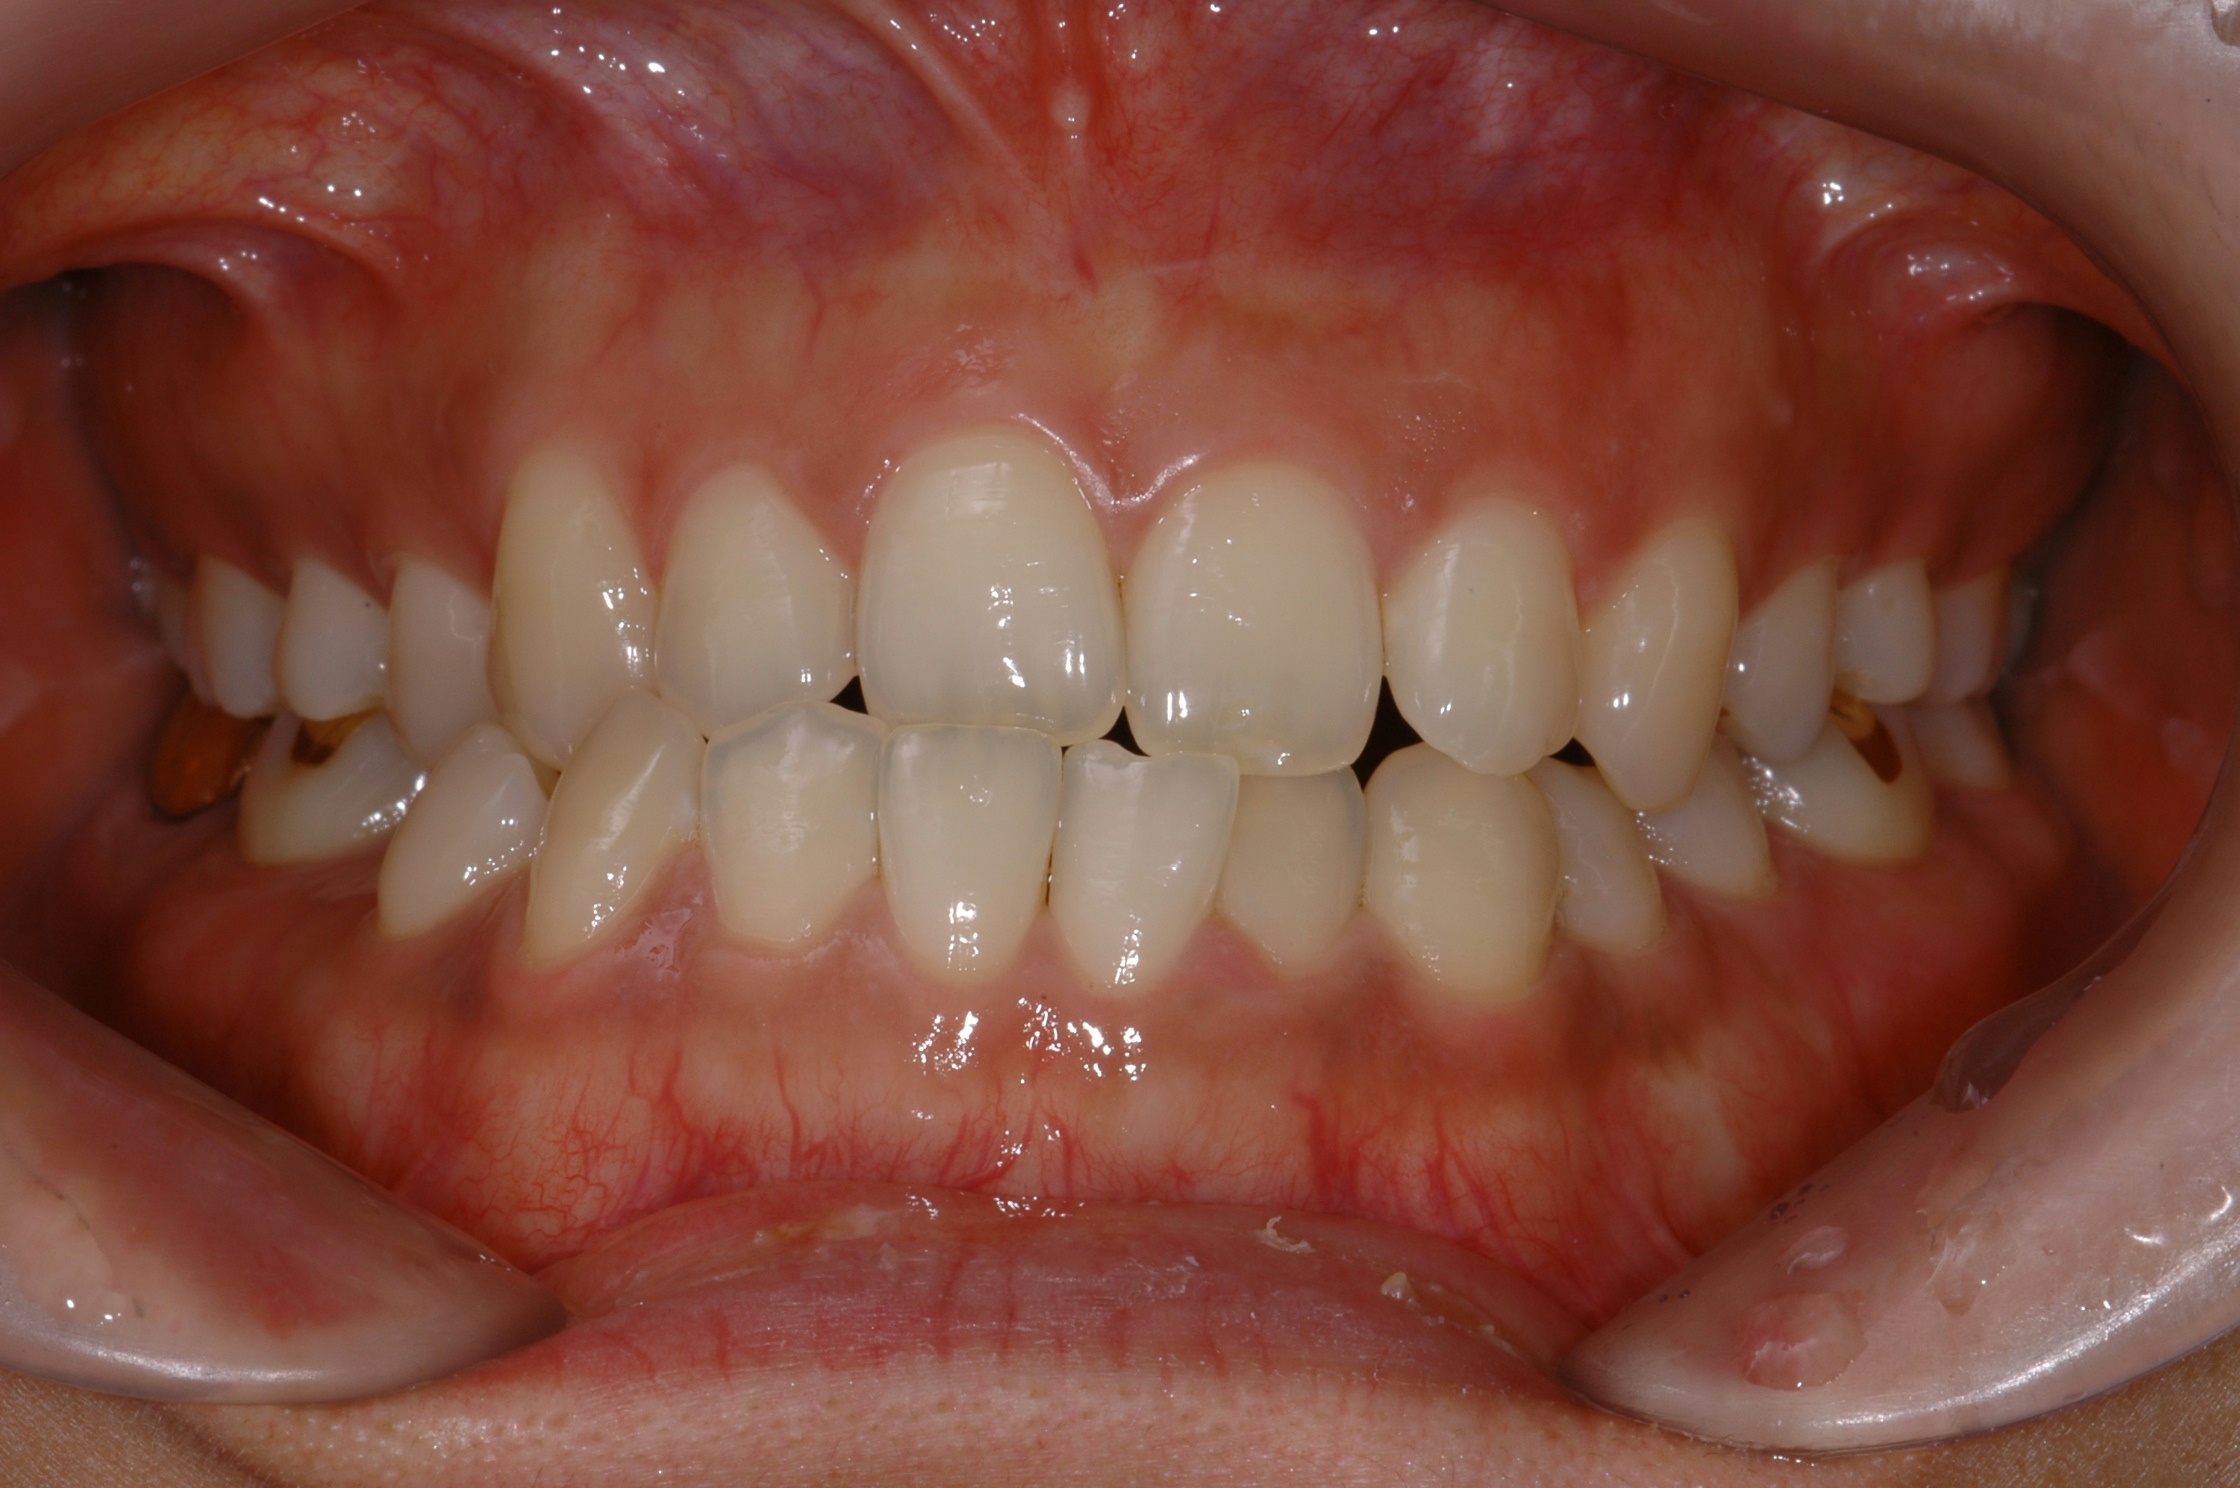

치료 전 사진입니다.